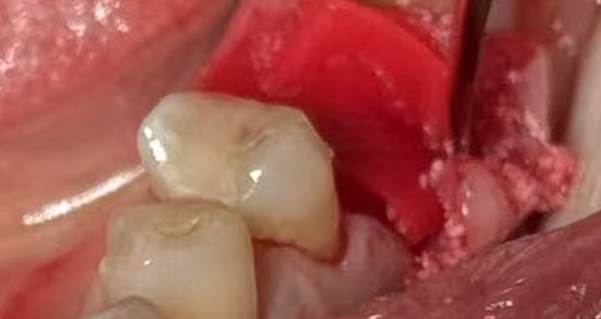

3. During the implant placement, a certain degree of bone and soft tissue deficiency was identified in the edentulous area. Consequently, bone graft (0.25g) and a collagen membrane were simultaneously placed.

Bone and soft tissue deficiency in the edentulous area

Placement of 0.25g bone graft during implantation

Placement of one collagen membrane during implantation